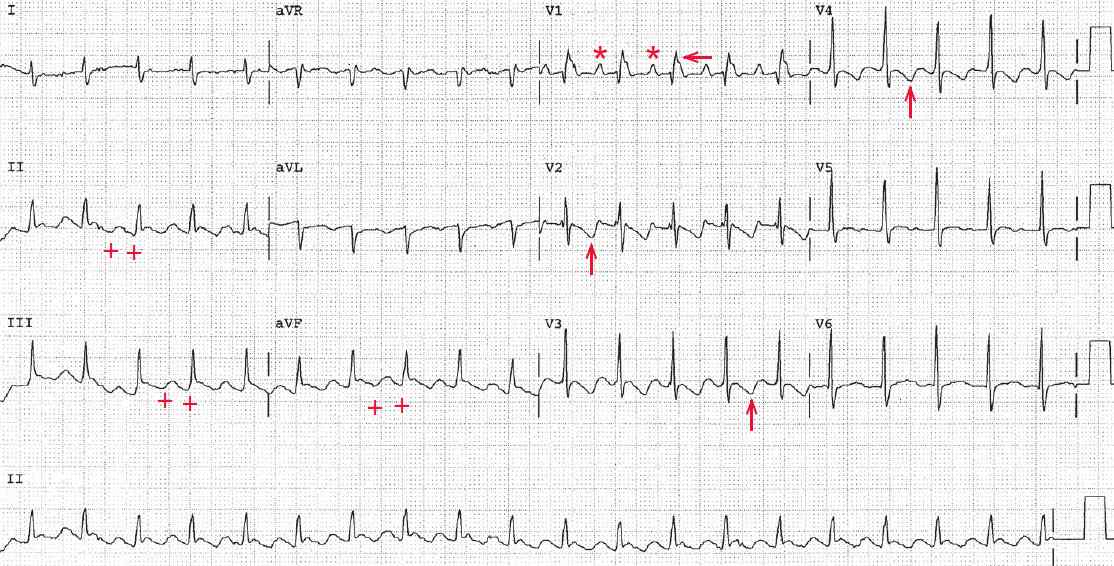

The ECG shows a regular rhythm at a rate of 130 bpm. The QRS complex has a normal duration (0.10 sec), although in lead V1 it appears to be longer 0.14 sec, and has a morphology suggestive of right bundle branch block (RSR′ morphology in lead V1). However, the S waves in leads I and V5-V6 are not as wide as the R′ waveform in lead V1 (←).

The axis is normal (+90°), with a biphasic QRS complex in lead I and a positive QRS complex in lead aVF. Although no distinct P waves are seen in leads II, III, and aVF, the baseline appears to have undulations (saw-tooth–like) that are suggestive of flutter waves (+).

In lead V1 a distinct atrial waveform can be seen before each QRS complex (*). The terminal portion of the R′ waveform in lead V1 has obvious notching (↓), suggesting another atrial waveform. Indeed, when the intervals are measured they are all regular. The QT/QTc intervals are normal (280/410 msec).